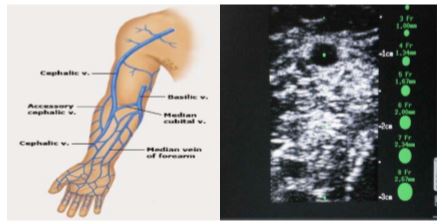

Incluye el procedimiento de inserción ecoguiado, con imágenes.